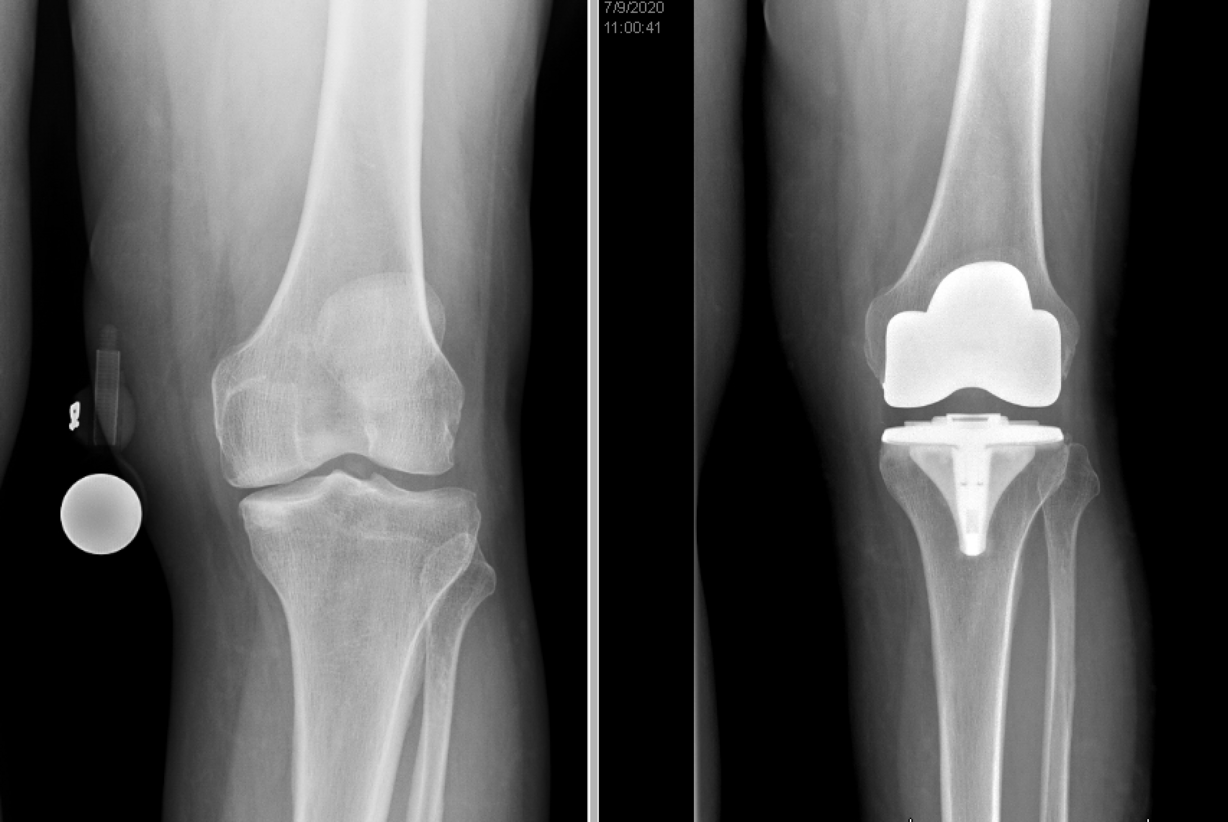

In 2013, he retired, with plans to travel, go to the movies and above all fly fish in his home state of Utah and Montana. He'd just had his right knee replaced after "it had gotten real bad." But seven years later, in late 2019, it was his left knee that started hurting.

The then-68-year-old went to see Christopher Pelt, MD, an orthopedic surgeon specializing in joint replacement surgery, at the University Orthopaedic Center. Pelt told him he needed surgery if he wanted to keep walking.

But for Tony, his surgery was hardly a matter of choice. When he walked, his knee popped out of joint and he couldn't climb stairs anymore. "I have a home, I go out and mow the lawn, take care of the gardening," he says. "It got to where I didn't feel I could do that anymore. It just got to where I didn't want to walk anymore."

Pelt says Tony is reflective of a large number of patients. "It's easy to say it's just knee pain or knee arthritis. But when someone goes from caring for his family and house to not being able to walk because the pain is so severe, that's a big deal." Pelt argues that what has become apparent during the pandemic is that most surgeries performed by the Orthopedic Center are not elective. "And not to patients in particular," he says. "There's a huge difference in surgery done to enhance appearances on the one hand and allow people to work and walk and function in society on the other."